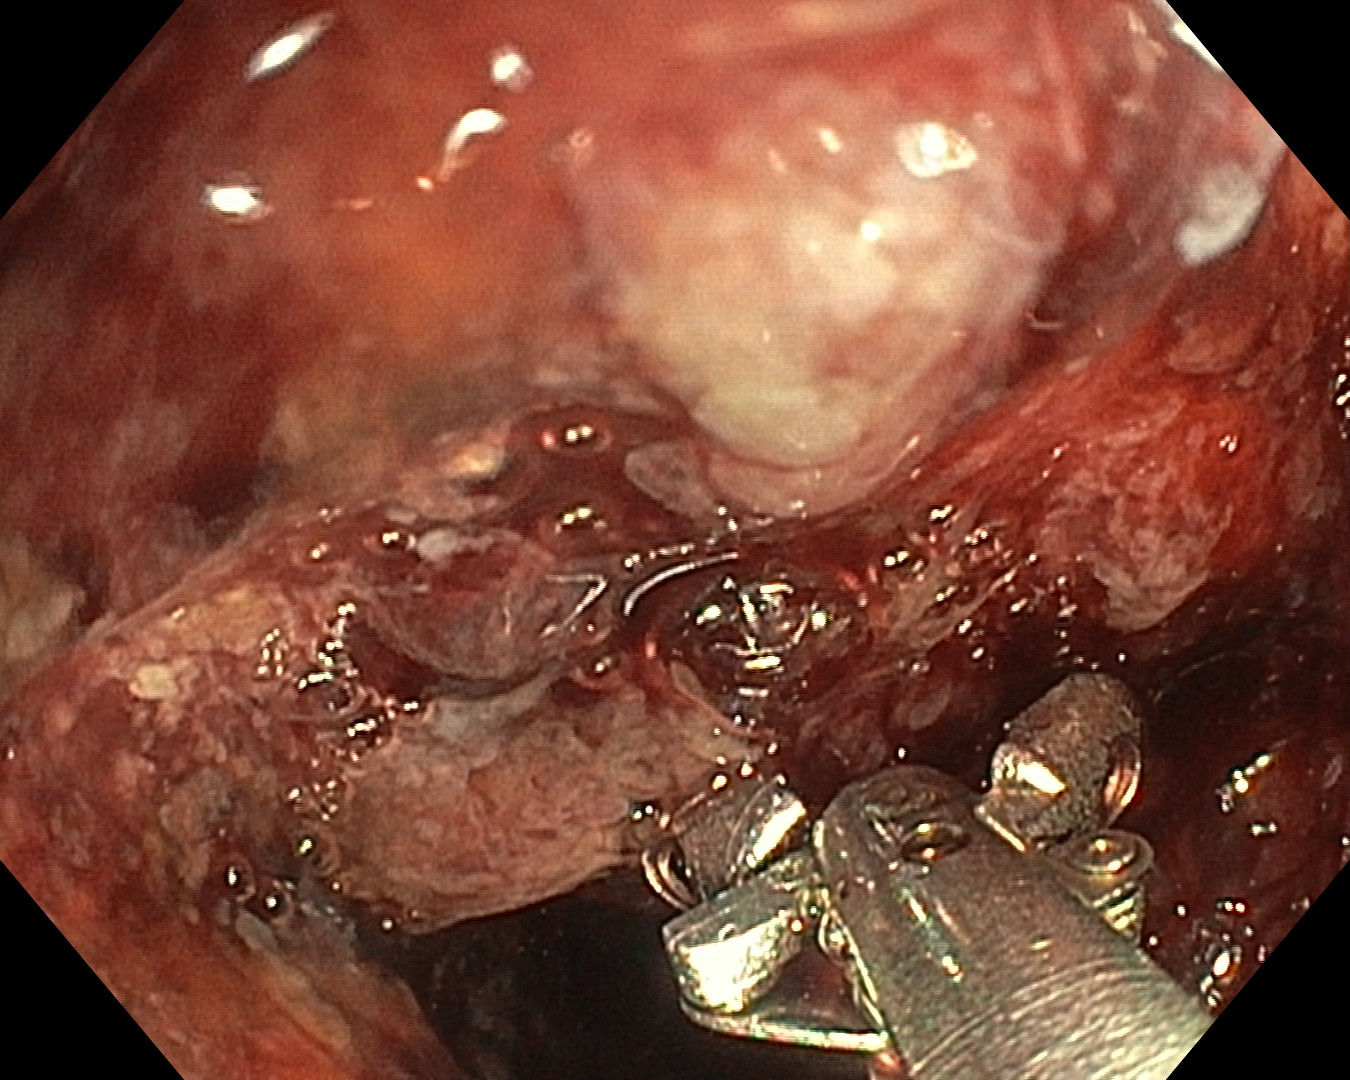

Mai mult, aparatul pe care îl folosim permite recoltarea de biopsii, obținerea, practic, a unui fragment bioptic, ce este apoi analizat de histopatologi. În plus, se pot efectua diferite tehnici intervenționale. De exemplu, oprirea unei hemoragii prin aplicarea de hemoclipsuri, coagularea cu argon plasmă sau excizia de polipi”, explică conf. dr. Christian Banciu, șeful Secției Medicină Internă a Spitalului Clinic CF Timișoara.